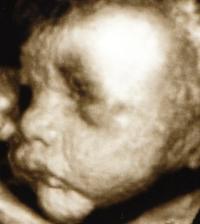

Začali sme sa nanovo snažiť tak uvidíme ako dlho to potrvá dostať sa k cielu.15.12.2009 som dostala taký predčasný vianočný darček // na testíku. 18.12 boli sme u dr ešte nebolo nič vidieť tak maminu pochytila panika ale hcg je 465 takže tehu sme len ešte malíčko a zase sa bojím či je to ok:-// 23 sme boli u dr chytili ma ladviny tak som dostala ant. ale fazulka sa má zatial ok je presne tak kde má byť vačok má 8 mm a už je tam aj základ bábenka.🙂)) Aby ani druhé bábenko nezaostávalo za Kubkom tak mamine je zase poriadne zle už aby bol 12 tt a trochu to prešlo. 14.1 boli sme kontrole všetko ok krásne bilo srdiečko. Dostali sme tehu knižku a prenatal box. 28.1 nás čaká ultrazvuk tak sa už moc teším.Stále my je dosť špatne a už aj vraciam čo už:-/// 2.2. dnes sme boli na utz všetkoje v poriadku aj ked dr najskôr bábo nemohol nájsť po chvílke ho predsa vypátral. všetko je ok bábenko meria 6,68 cm a crl má 4,6 cm. tak na dalšej kontrole sme sa dozvedeli že naše prekvapenie bude chlapček tak budeme mať Mateja- Maťka dalšia poradna za namy všetko ok dalšia nás čaká 7 apríla a konečne znova uvidíme drobčeka. Všetko dopadlo dobre Matejko je trošku večší ale hlavne je ok. 10.5 Gtt hádam budu dobré výsledky inak všetko v norme len bruško je trošku večšie o 2 týždne kontrola tak uvidíme na tvrdnutie sme dostali mange b6 2x dene tak hádam to pomože. Boli sme na sone 17.6 a Matko chce asi predbehnut porodnou váhou Kubka už teraz má 2107 g a aj ostatné rozmery su chválihodné inak je všetko v poriadku pekne si kopká a už sa moc tešíme